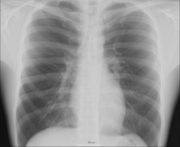

Human anatomy, physiology and biochemistry are complementary basic medical sciences, which are generally taught to medical students in their first year at medical school. Human anatomy can be taught regionally or systemically; that is, respectively, studying anatomy by bodily regions such as the head and chest, or studying by specific systems, such as the nervous or respiratory systems. The major anatomy textbook, Gray's Anatomy, has recently been reorganized from a systems format to a regional format, in line with modern teaching methods. A thorough working knowledge of anatomy is required by all medical doctors, especially surgeons, and doctors working in some diagnostic specialities, such as histopathology and radiology.